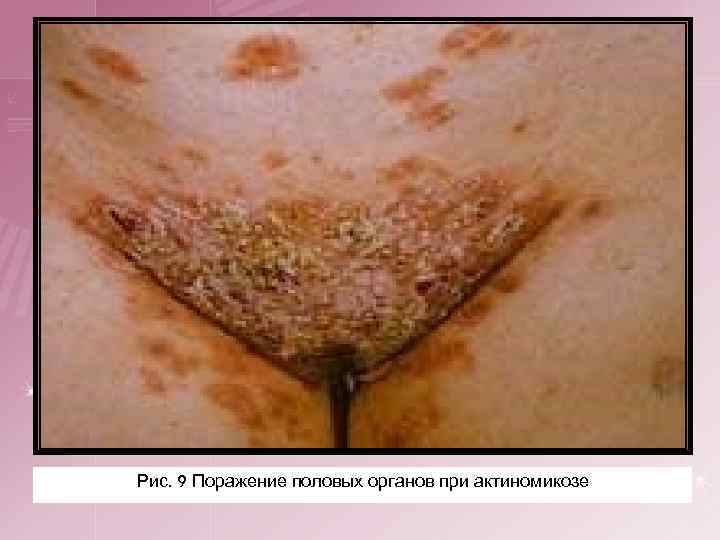

4. Актиномикоз половых и мочевых органов. Как правило, это вторичные поражения при распространении инфильтрата при абдоминальном актиномикозе. Первичные актиномикозные поражения половых органов встречаются очень редко.

Рис. 8 Поражение половых органов при актиномикозе

Рис. 9 Поражение половых органов при актиномикозе